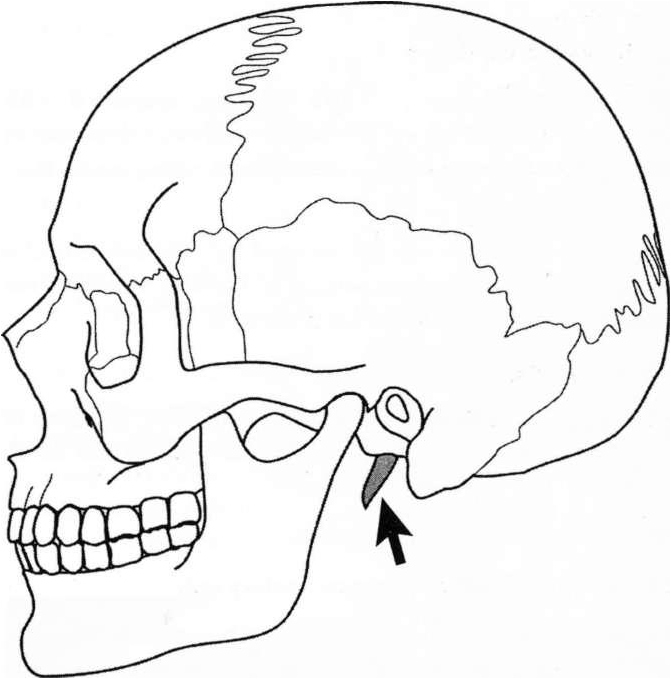

A surgeon utilizes an infratemporal fossa approach to

remove a large infiltrating tumor of the cranial base. He

comes across the shaded structure depicted by the arrow below. How many muscles attach to this structure?

B. 3

Which cranial nerves innervate these muscles?

B. VII, IX, XII

. How many ligaments attach to this structure?

B. 2

The styloid process gives rise to the stylohyoid

(VII), styloglossus (XII), and stylopharyngeal muscles

(IX) of the visceral neck as well as the stylomandibular and stylohyoid ligaments. It is a remnant of the second brachial arch